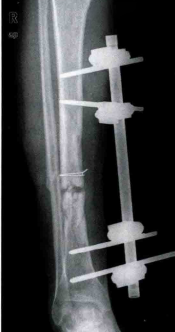

③缺损性骨不连

两骨断端间存在骨块缺损,骨折端虽有活力但却不能越过缺损处形成连接,经过一段时间后骨折端萎缩,无连续性骨痂,通常继发于开放骨折、骨髓炎死骨形成或者骨肿瘤切除术。